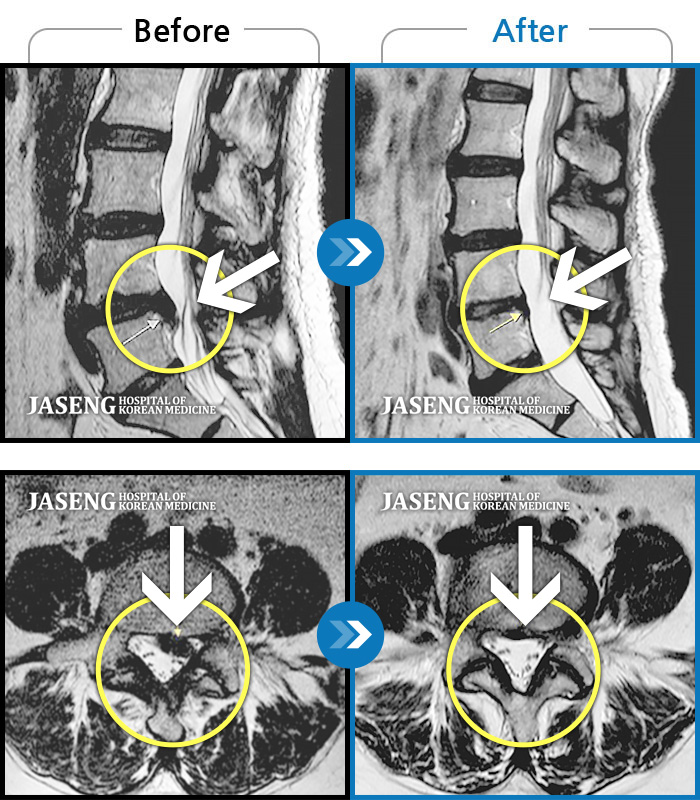

Before

After

목부터 좌측 어깨까지 통증이 심해요

2022.07.04 ~ 2024.09.02